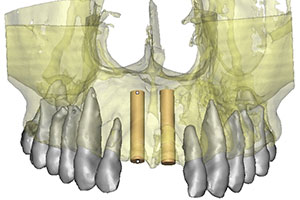

Se realiza tomografía e imagen tridimensional 3D, observamos además de la lesión traumática, que la paciente tiene raíces enanas.

Decidimos: bajo anestesia local. previa asepsia y antisepsia, la limpieza de los alvéolos y la colocación de paralelos e implantes dentales.se colocan sus mismas coronas naturales para darle forma a los tejidos blandos y conservar papilas anatómicas.